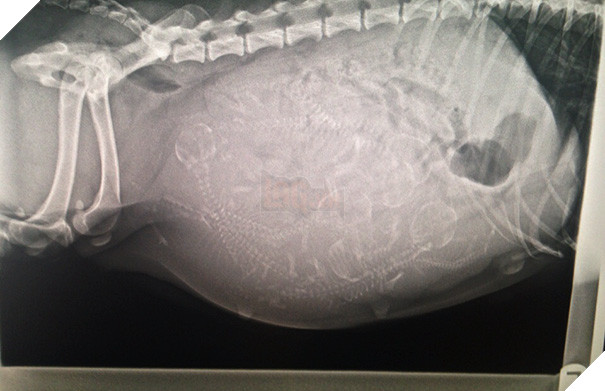

Một bà mẹ mèo đang mang thai. Thời gian thai kỳ của mèo khoảng 56 - 71 ngày, trung bình kéo dài khoảng 67 ngày và chúng có thể "sản xuất" 3 - 4 lứa mỗi năm.

Một hình ảnh khác về mèo mang thai. Có những loài vật mang thai 14 ngày là sinh nở, nhưng cũng có loài động vật cần 23 tháng để "mang nặng đẻ đau" khúc ruột của mình.